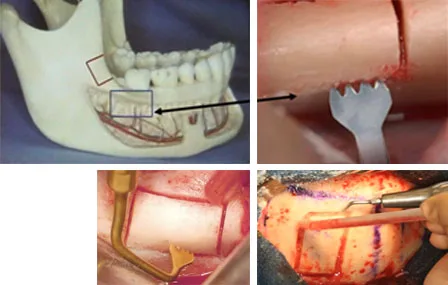

Implantologie : prélèvement du greffon crânien ; prélèvement du greffon mandibulaire (ramus)

OSBM ostéotomie Sagittale des Branches Montantes